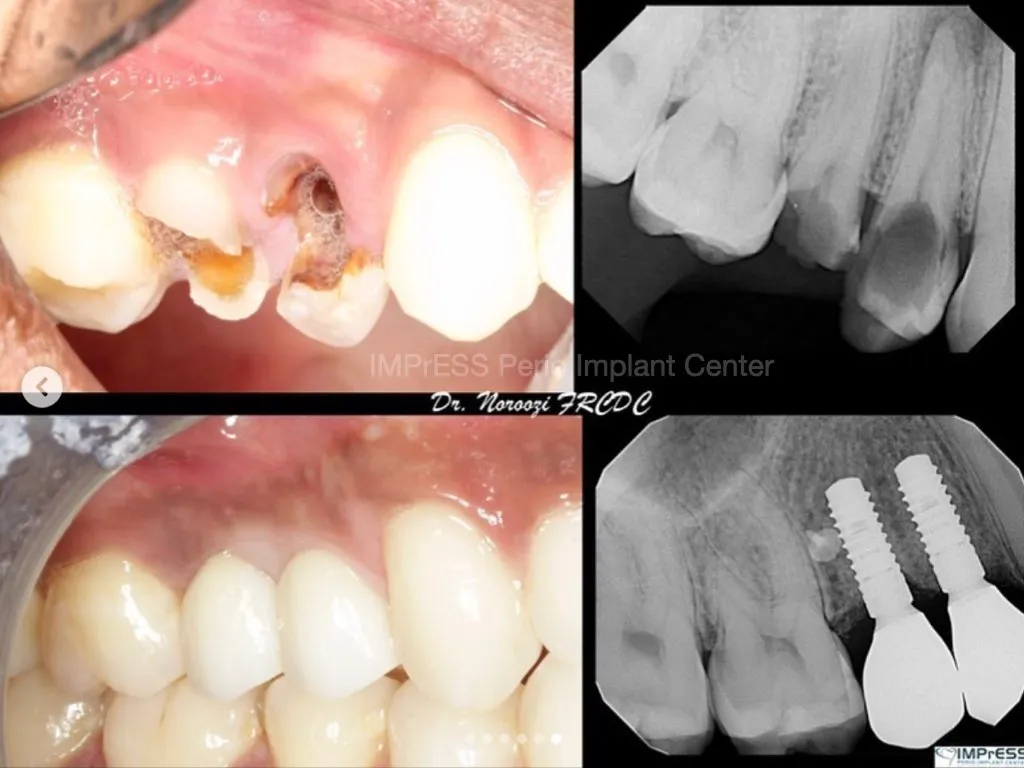

Immediate Implant Placement in Molar Extraction Site

IMPrESS Perio Implant Center Dr. Noroozi Vancouver Periodontist Implant Specialist Burnaby BC

immediate implant placement in molar site Dr. Noroozi